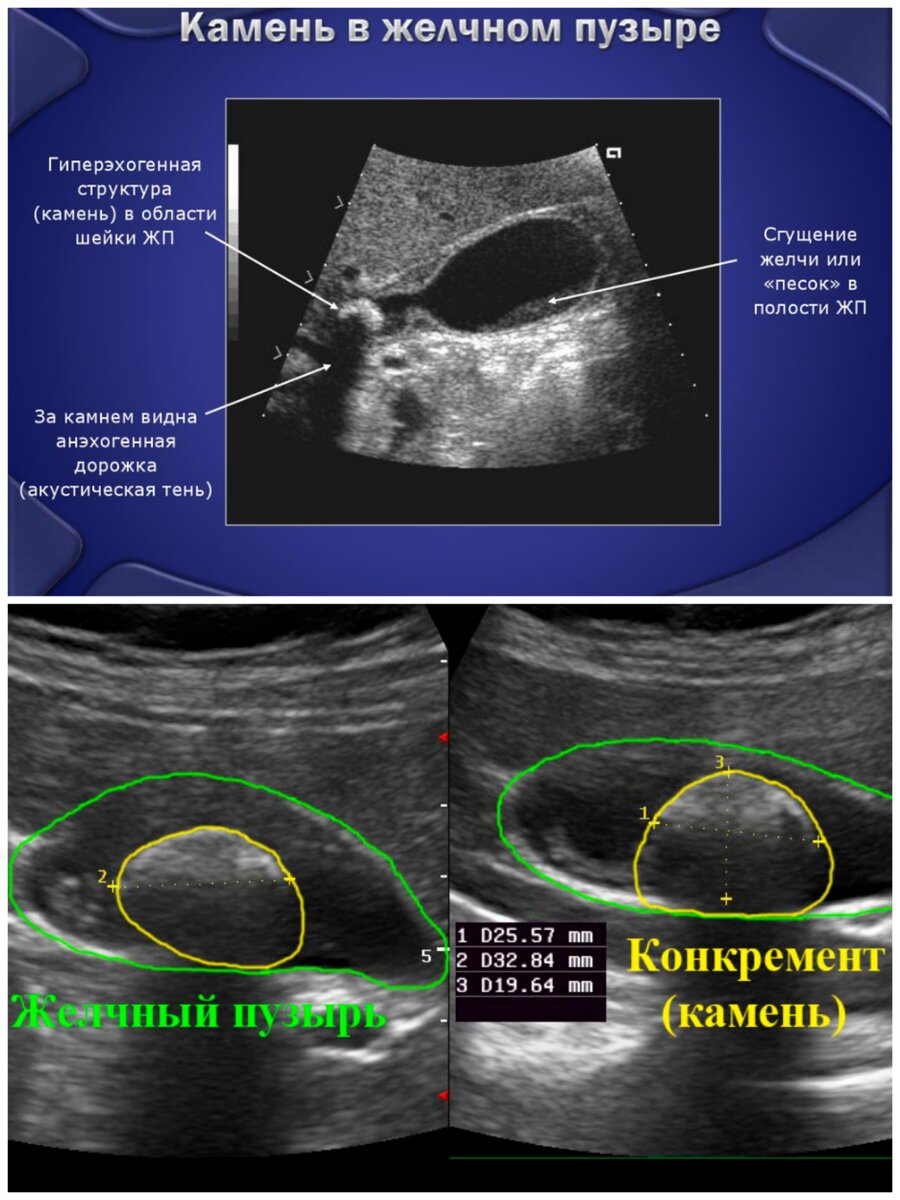

Для точного определения размеров и расположения камней назначается УЗИ пузыря и холедохоскопия.